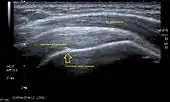

Ultrasound

There are several advantages of ultrasound. It is relatively cheap, does not emit any radiation, is accessible, is capable of visualizing tissue function in real time, and allows the performance of provocative maneuvers in order to replicate the patient’s pain.[26] Those benefits have helped ultrasound become a common initial choice for assessing tendons and soft tissues. Limitations include, for example, the high degree of operator dependence and the inability to define pathologies in bones. One also has to have an extensive anatomical knowledge of the examined region and keep an open mind to normal variations and artifacts created during the scan.[27]

After the introduction of high-frequency transducers in the mid-1980s, ultrasound has become a conventional tool for taking accurate and precise images of the shoulder to support diagnosis.[29][30][31][32][33]

Adequate for the examination are high-resolution, high-frequency transducers with a transmission frequency of 5, 7.5, and 10 MHz. To improve the focus on structures close to the skin an additional "water start-up length" is advisable. During the examination the patient is asked to be seated, the affected arm is then adducted and the elbow is bent to 90 degrees. Slow and cautious passive lateral and/or medial rotations have the effect of being able to visualize different sections of the shoulder. In order to also demonstrate those parts which are hidden under the acromion in the neutral position, a maximum medial rotation with hyperextension behind the back is required.[34]

To avoid the different tendon echogenicities caused by different instrument settings, Middleton compared the tendon’s echogenicity with that of the deltoid muscle, which is still lege artis.[35][36]

Usually the echogenicity compared to the deltoid muscle is homogeneous intensified without dorsal echo extinction. Variability with reduced or intensified[37] echo has also been found in healthy tendons. Bilateral comparison is very helpful when distinguishing and setting boundaries between physiological variants and a possible pathological finding. Degenerative changes at the rotator cuff often are found on both sides of the body.[38] Consequently, unilateral differences rather point to a pathological source and bilateral changes rather to a physiological variation.[36]

In addition, a dynamic examination can help to differentiate between an ultrasound artifact and a real pathology.[39]

To accurately evaluate the echogenicity of an ultrasound, one has to take into account the physical laws of reflection, absorption and dispersion. It is at all times important to acknowledge that the structures in the joint of the shoulder are not aligned in the transversal, coronal or sagittal plane, and that therefore during imaging of the shoulder the transducer head has to be held perpendicularly or parallel to the structures of interest. Otherwise the appearing echogenicity may not be evaluated.[40]

![]() Longitudinal ultra sonography of the supraspinatus tendon |